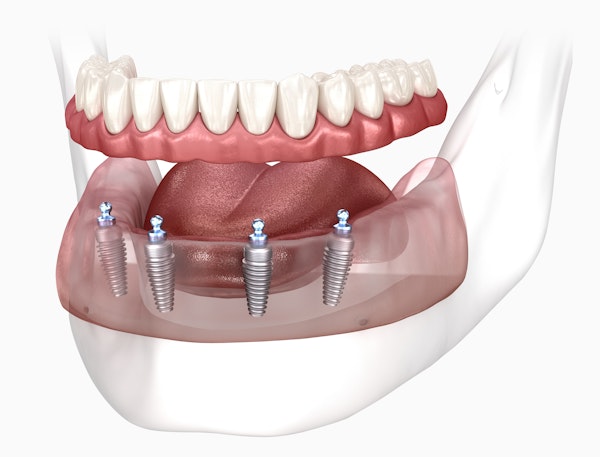

All-on-4 Dental Implants

For patients who may not qualify for traditional implant-supported dentures, our practice offers All-on-4® dental implants. This method involves using four implant posts versus six to eight. Two of the four posts are placed at a strategic angle to maximize existing bone material. In many cases, All-on-4 patients do not have to undergo preparatory bone grafting.

Dental implants are surgically placed directly into the jawbone. A single missing tooth can be replaced with a dental implant that supports a dental crown. The abutment is secured to the restoration, firmly holding it in place so the patient doesn't have to worry about it coming loose. They can then enjoy restored dental function, improved aesthetics, and preserved jawbone density.